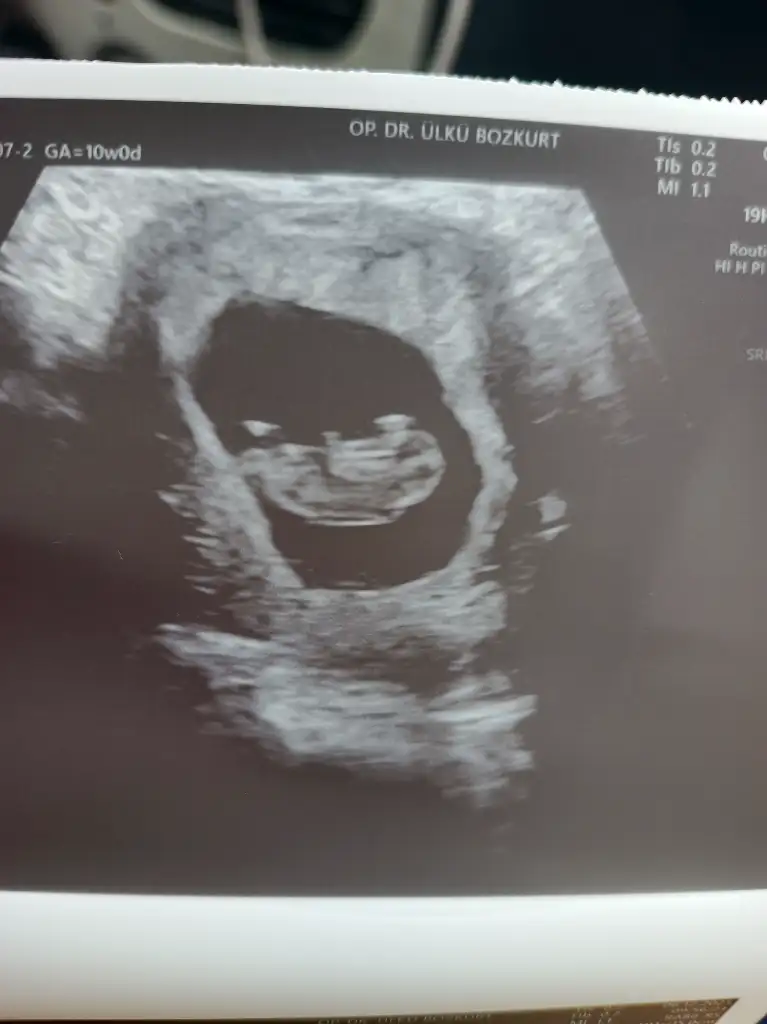

Uyy maşallah miniğimizeeKızlar dün kontrol vardı 10+0 maşşallahınızı alırım ❤ elleri kolları hareket ediyordu çok mutlu olduk valla. İkili tarama testi vakti yaklaşıyor. Bu konuda ne düşünüyorsunuz. Sonuç ne olursa olsun bebeği aldırma taraftarı olabilecek biri değilim. O zaman bu testi yaptırmanın anlamı var mı? Ne düşünüyorsunuz bu konuda